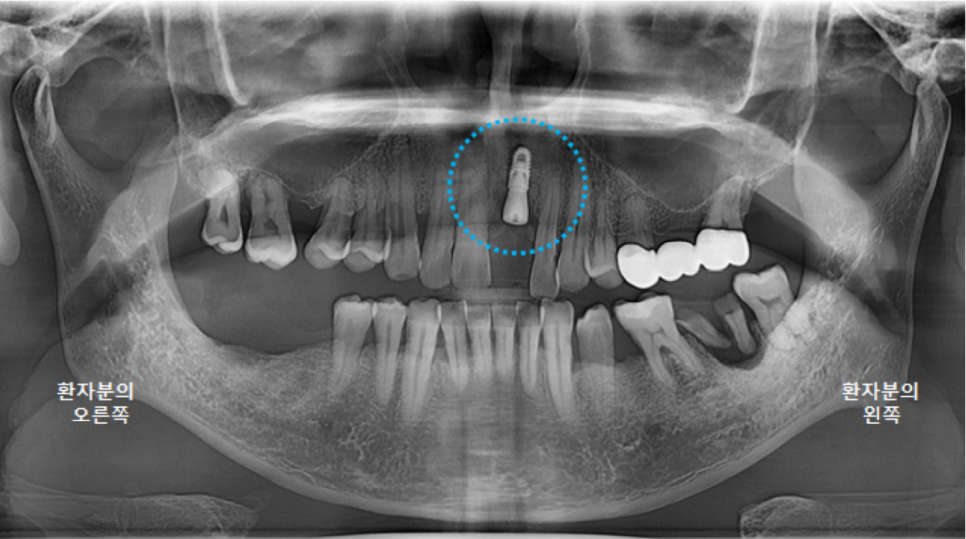

앞니 임플란트 수술 직후 파노라마 엑스레이 사진입니다.

양옆의 치아 관계도 좋고 뼈이식도 잘 되었습니다. ^^

깨끗하게 뿌리조각과 염증을 제거하고 파노라마 엑스레이를 촬영했습니다.

(사진은 왼쪽어금니 발치와 오른쪽 어금니 수술 이후 촬영한 사진입니다^^)

뼈가 많이 녹아 있는 상태여서, 나중에 임플란트 식립시에 뼈이식이 꼭 필요할 것으로 보입니다.